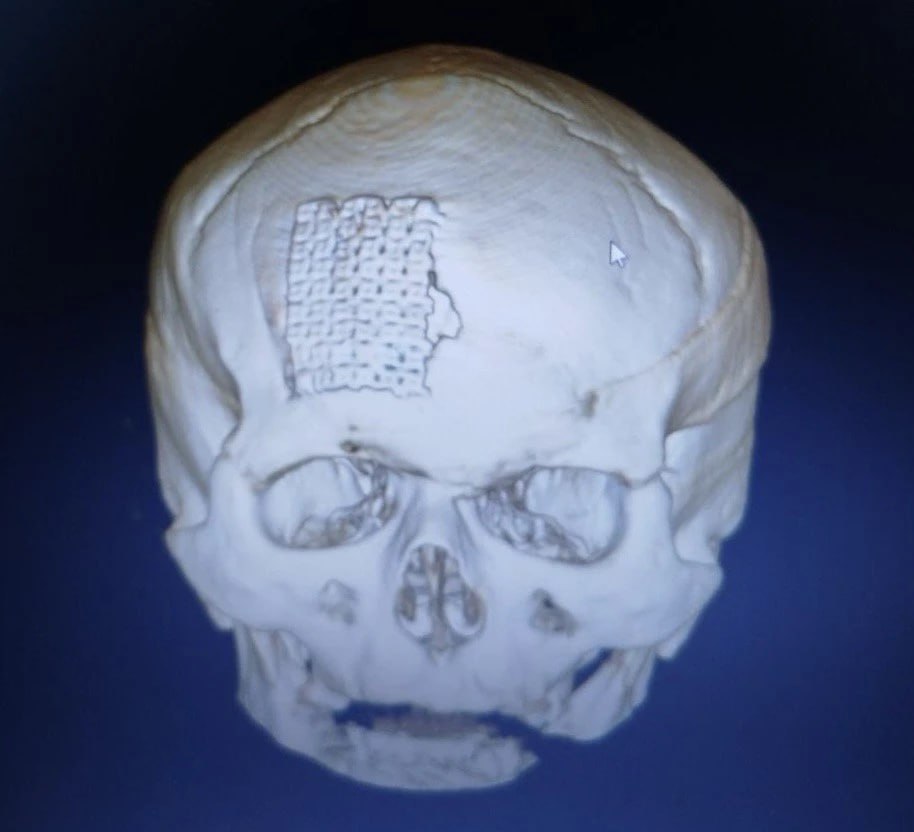

Нейрохирурги смогли удалить опухоль, сохранив все важные сосуды, очистили пораженные лобные пазухи, а также закрыли полость черепа и перекрыли сообщение с носом и внешней средой тканями пациента с бедра. Для восстановления кости лба была использована титановая пластина.